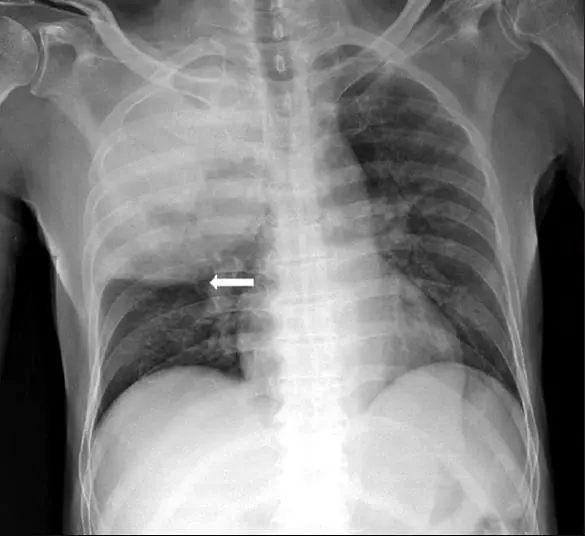

Quais os achados radiológicos mais comuns na pneumonia comunitária?

Infiltrado pulmonar do tipo alveolar broncopneumônico com presença de broncograma aéreo